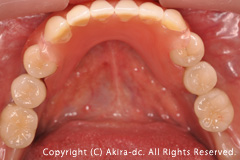

インプラントの上部構造(被せ物)6本です。 |

アバットメント(土台) |

インプラント上部構造(被せ物)完成 |

インプラント上部構造(被せ物)装着 |